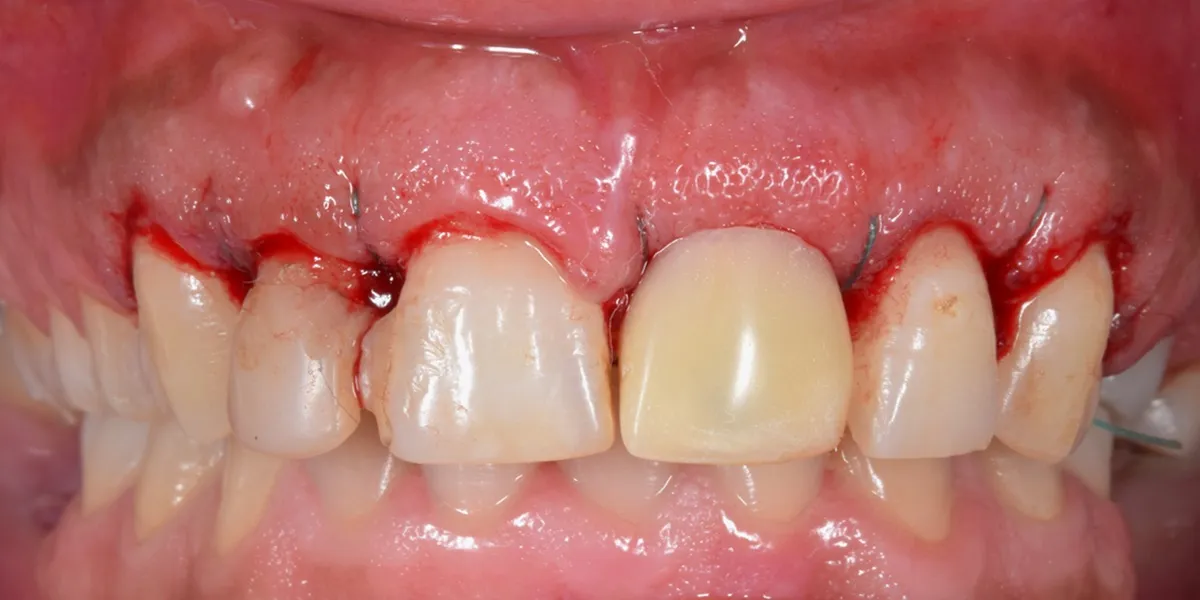

درمان های زیبایی مانند کامپوزیت دندان اگرچه با هدف بهبود ظاهر لبخند انجام میشوند، اما در صورت بی توجهی به اصول علمی و بیولوژیک لثه، میتوانند باعث تحریک بافت های اطراف دندان شوند. التهاب لثه بعد از کامپوزیت ممکن است به صورت قرمزی، تورم، خونریزی هنگام مسواک زدن یا حتی درد خفیف تا شدید بروز کند. این علائم هشداری هستند که نباید نادیده گرفته شوند، زیرا سلامت لثه نقش کلیدی در ماندگاری درمان های زیبایی دارد.

یکی از مهم ترین دلایل التهاب لثه بعد از کامپوزیت دندان، تماس مستقیم یا غیر اصولی مواد ترمیمی با لثه است. زمانی که کامپوزیت بیش از حد به ناحیه لثه نزدیک باشد یا لبه های آن به درستی پولیش نشده باشند، بافت لثه تحریک میشود. این تحریک مداوم میتواند به مرور زمان باعث التهاب لثه بعد از کامپوزیت شود و حتی شرایط را برای تجمع پلاک میکروبی فراهم کند.

در شرایطی که کامپوزیت به درستی کانتور نشده باشد، فضای مناسبی برای تمیز کردن دندان باقی نمیماند. این مسئله باعث میشود باکتری ها در ناحیه اتصال دندان و لثه تجمع پیدا کنند و التهاب تشدید شود. توجه به جزئیات فنی در هنگام انجام درمان، نقش بسیار مهمی در پیشگیری از التهاب لثه بعد از کامپوزیت دارد.